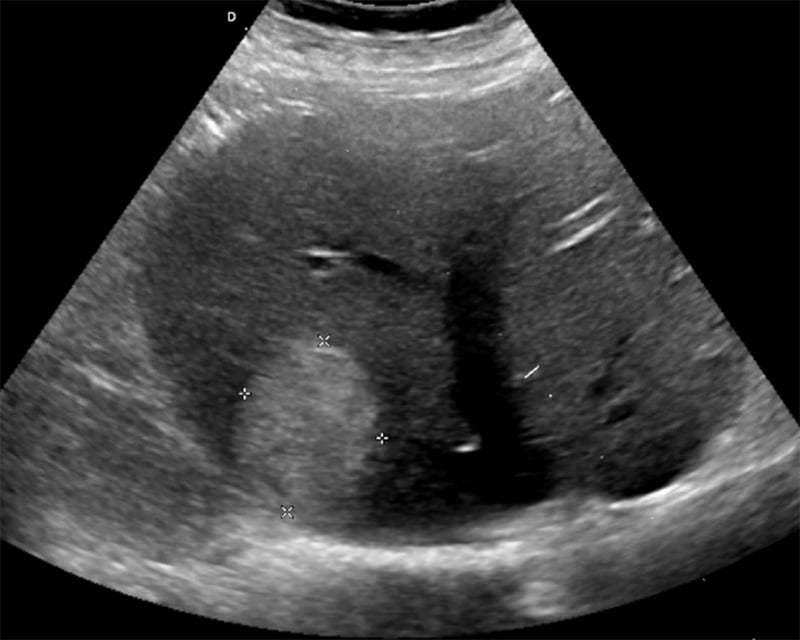

Figure 24A. Large pyogenic liver abscess with heterogenous material swirling inside the lesion, and “dirty shadowing.”

Figures 24B & 24C. Large pyogenic liver abscess with heterogenous material swirling inside the lesion, measuring >11cm in the long dimension (B) and >5cm in the shorter dimension (C).